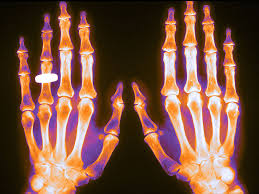

Esta es la segunda entrega de la Folia DOC  dedicada a osteoporosis. La primera se enfocó en el diagnóstico, prevención y medidas no farmacológicas, y en esta se aborda el tratamiento farmacológico. El mismo variará según el riesgo estimado de fractura, la consideración de la eficacia y seguridad de los diferentes fármacos, la conveniencia de su administración y las preferencias de las pacientes. FoliaDOC, Fundación FEMEBA, 27 de enero de 2025.

El objetivo de esta Folia.doc es brindar recomendaciones basadas en evidencia sobre prevención y tratamiento de osteoporosis considerando la eficacia, efectividad y segu­ridad de los medicamentos disponibles. Estas recomen­daciones son válidas tanto para el equipo de salud de atención primaria como para especialistas en el segundo nivel de atención, ya que el tema de prevenir y tratar os­teoporosis y fracturas por fragilidad los involucra a todos. FoliaDoc , Fundación Femeba, 16 de octubre de 2024